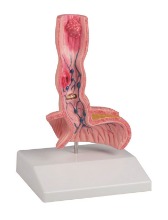

위궤양 모형(K217)

143,000원

식도질환 모형(K218)

141,000원